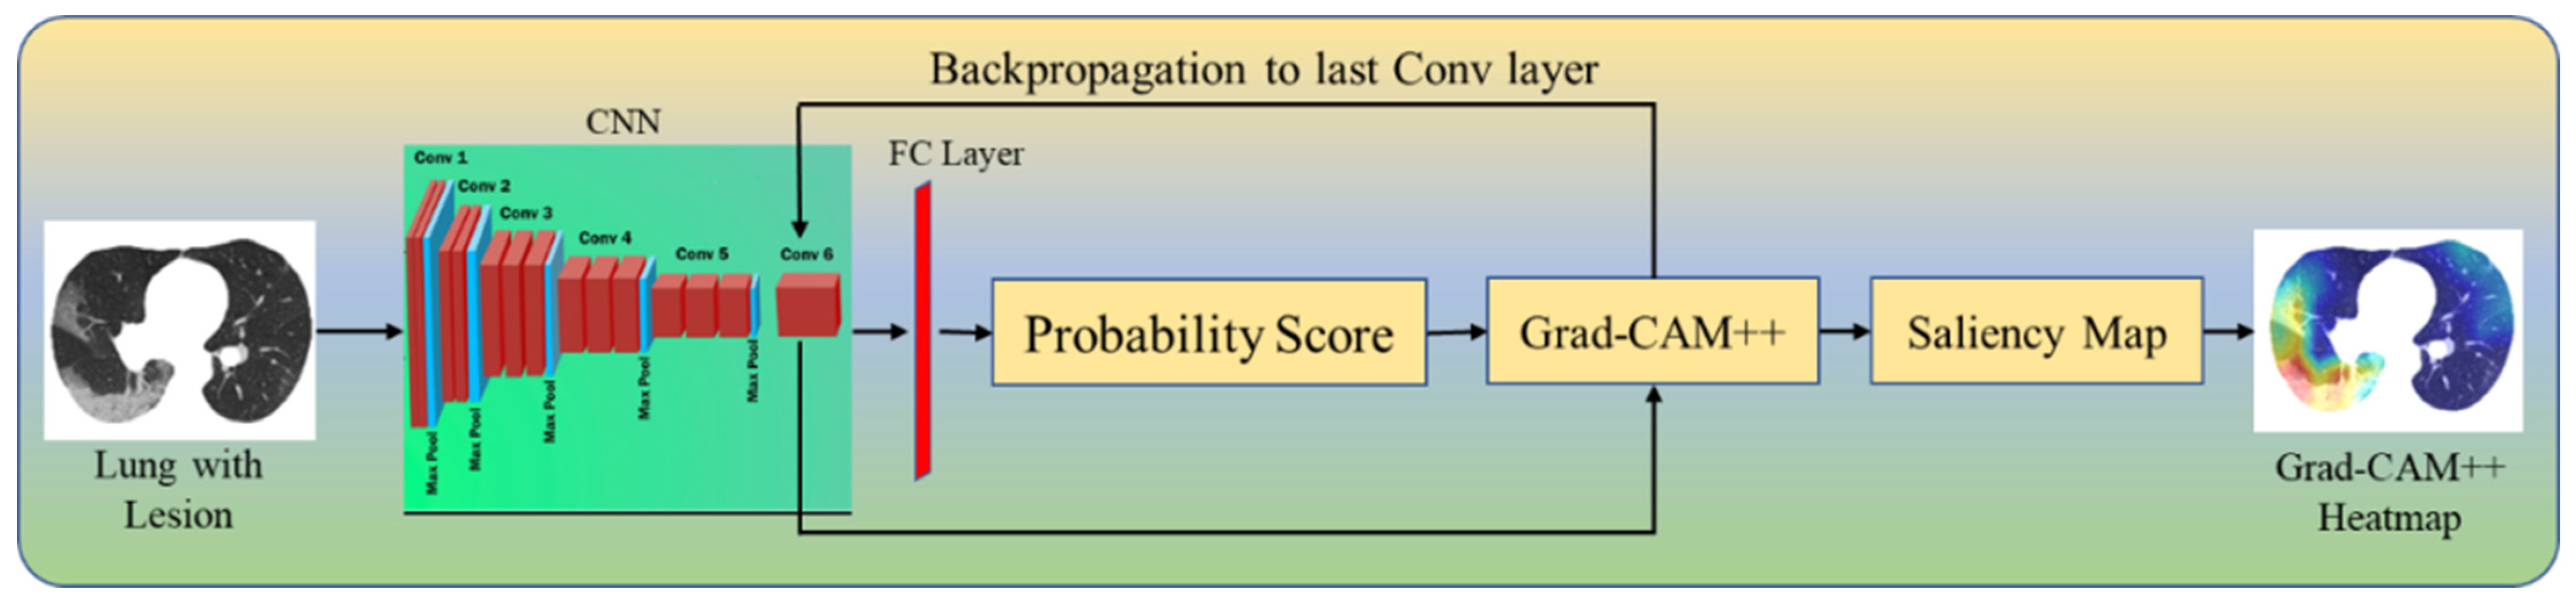

Four CAM Techniques in Cloud-Based Explainable Artificial Intelligence System

4.4. A Special Note on Four CAM Models